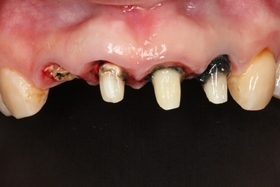

治療前,X光片及口內照片。

舊牙冠拆除後,右上側門牙及左上正中門牙斷裂。